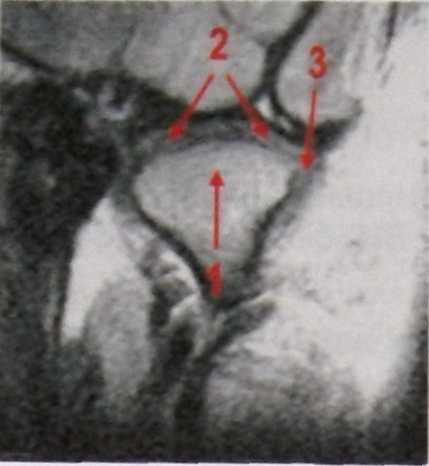

| Рис. 8.71. Т1 взвешенная томограмма ВНЧС в кософронтальной проекции: 1- мыщелок нижней челюсти; 2- внутрисуставной диск; 3- латеральная коллатеральная связка |